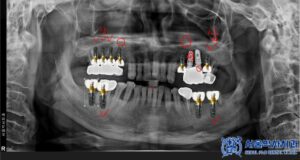

발치를 진행한 후, 우선적으로 하악 좌우 어금니

부위부터 무절개 임플란트를 총 4개 심었습니다.

이 과정에서는 뼈 이식도 병행하였습니다.

이후 상악 좌우도 순차적으로 치료를 진행하였으며,

기존 타 치과에서 심은 왼쪽 위 작은 어금니 위치의

임플란트와 파절된 인접 보철물도

함께 제거하였습니다.

상악 좌우는 모두 뼈이식을 동반한

무절개임플란트를 총 6개 식립하였습니다.

이처럼 총 10개의 무절개 임플란트를

식립하게 되었는데요.

미리 3D CT를 통해 정밀한 위치를 컴퓨터로 분석하고,

고성능 3D프린터로 만든 “수술 가이드”를 이용해

임플란트를 심기 때문에 출혈과

통증이 적고 회복도 빠릅니다.

위 이미지는 실제 수술 중 수술가이드를

착용했던 모습으로,

임플란트가 정확한 각도로 식립될 수 있습니다.

무절개 방식은 특히 임플란트의 “식립 각도”를

정밀히 맞추는 데 큰 도움이 됩니다.